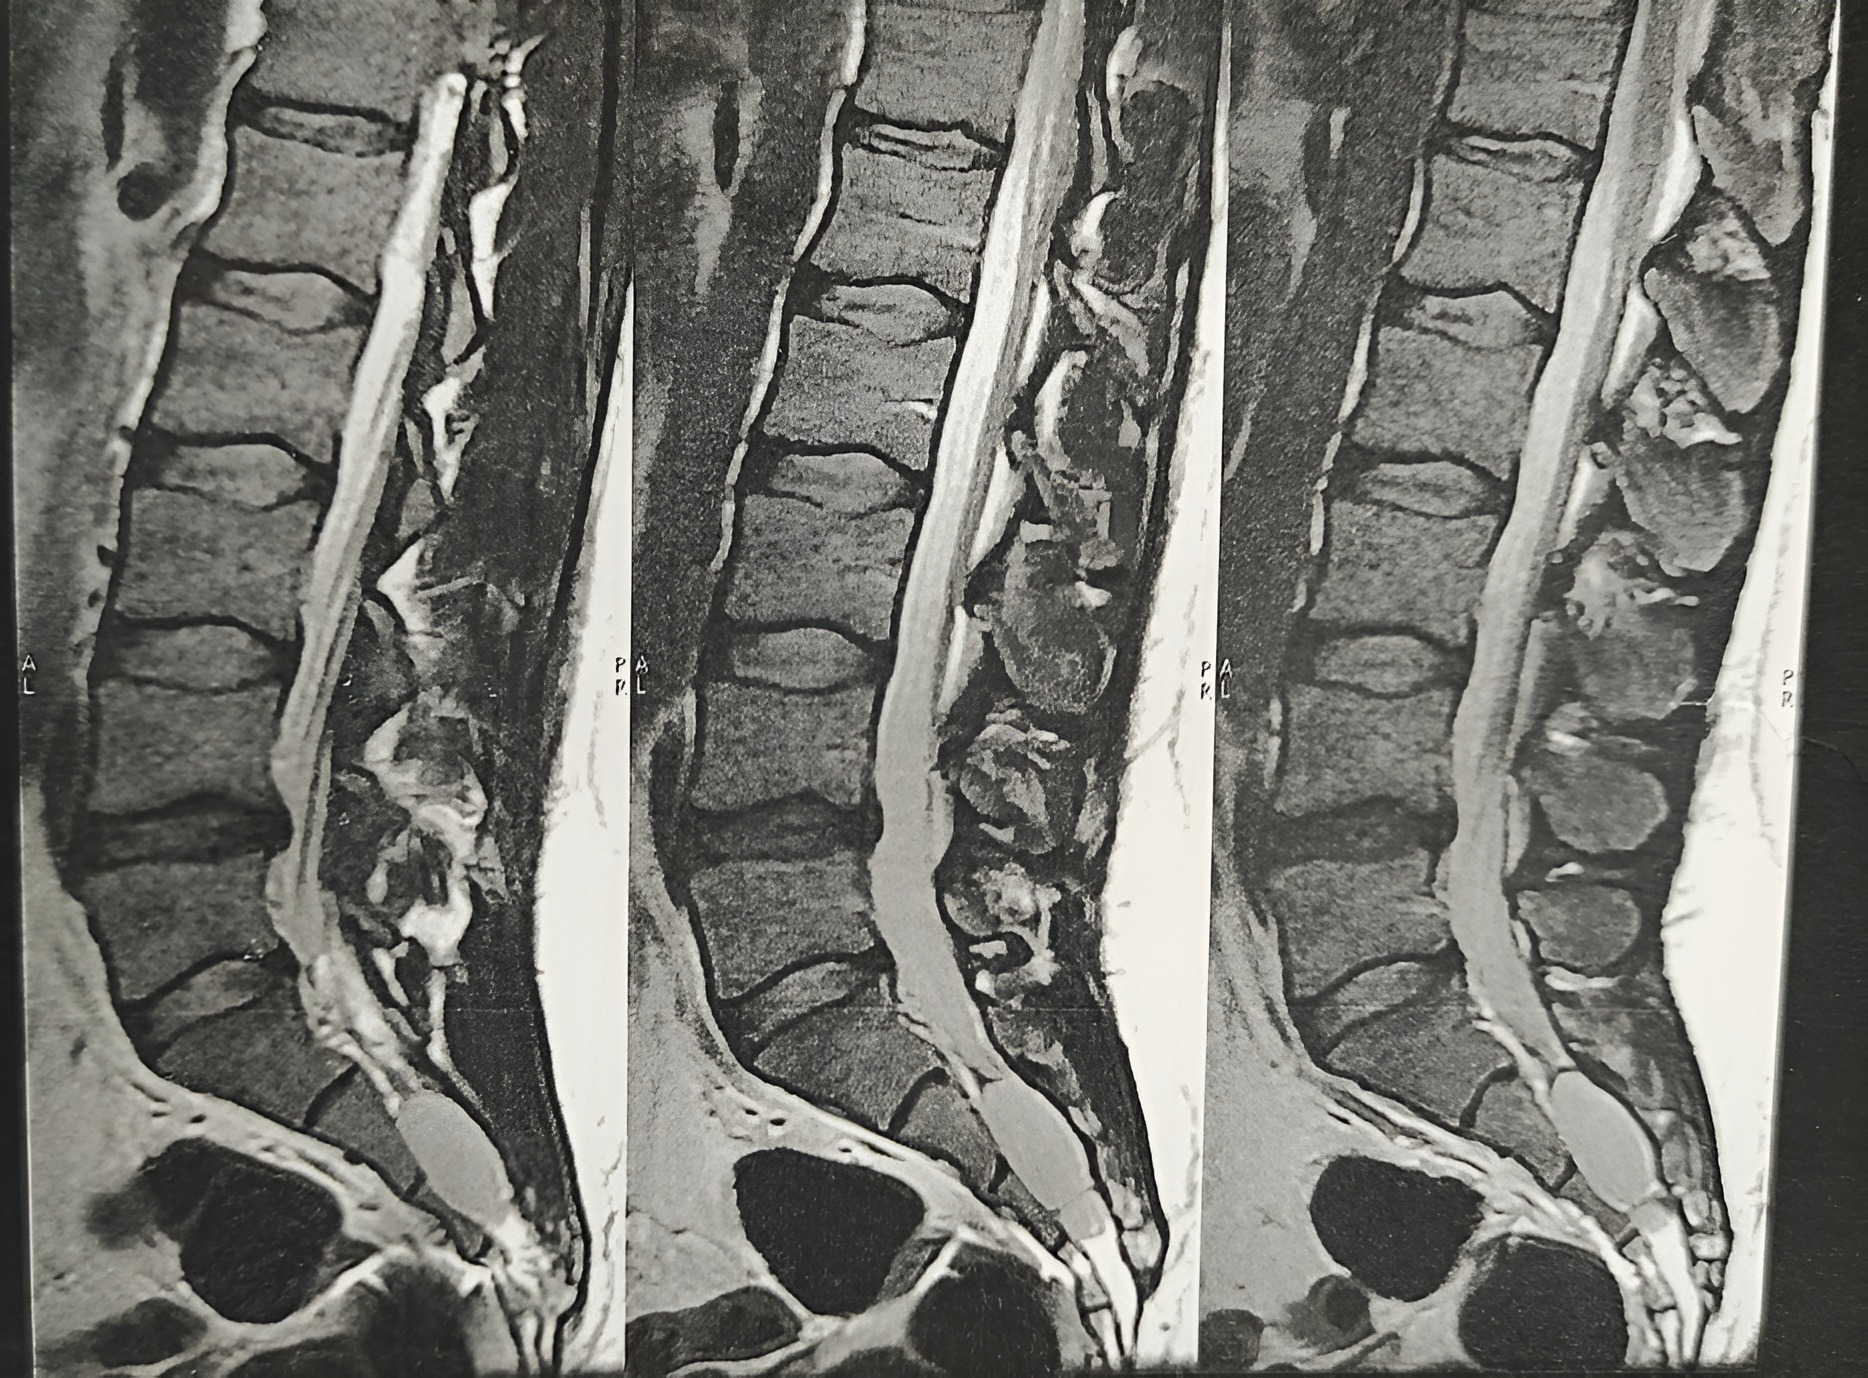

یک تاریخچه پزشکی کامل و معاینه فیزیکی معمولاً میتواند هر شرایط جدی را که ممکن است باعث درد شود را شناسایی کند. الکترومیوگرافی (EMG) می تواند به تعیین علت درد و درمان مناسب کمک کند. تصویربرداری پزشکی در بیشتر موارد مورد نیاز نیست، اما ممکن است برای رد علل خاص درد، از جمله تومورها و تنگی نخاع، تجویز شود. گاهی اوقات تشخیص علت کمردرد مزمن حتی پس از معاینه کامل دشوار است.

توموگرافی کامپیوتری (CT) می تواند ساختارهای بافت نرم را نشان دهد که در اشعه ایکس معمولی قابل مشاهده نیستند، مانند پارگی دیسک، تنگی نخاع یا تومورها.

میلوگرام تصویربرداری تشخیصی اشعه ایکس و سی تی اسکن را بهبود می بخشد. در این روش، بهترین متخصص ستون فقرات در تهران یک رنگ کنتراست به کانال نخاعی تزریق میکند که به نخاع و عصبهای ناشی از فتق دیسک کمر یا شکستگیها اجازه میدهد در عکسبرداری با اشعه ایکس یا سی تی اسکن دیده شوند.